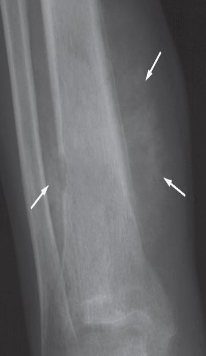

Spiculated (sunray) periosteal reaction in a case of

osteogenic sarcoma (arrows)

‘Onion skin’ periosteal reaction in a

case of Ewing’s sarcoma (arrows). Here

the periosteal new bone consists of

several distinct layers.